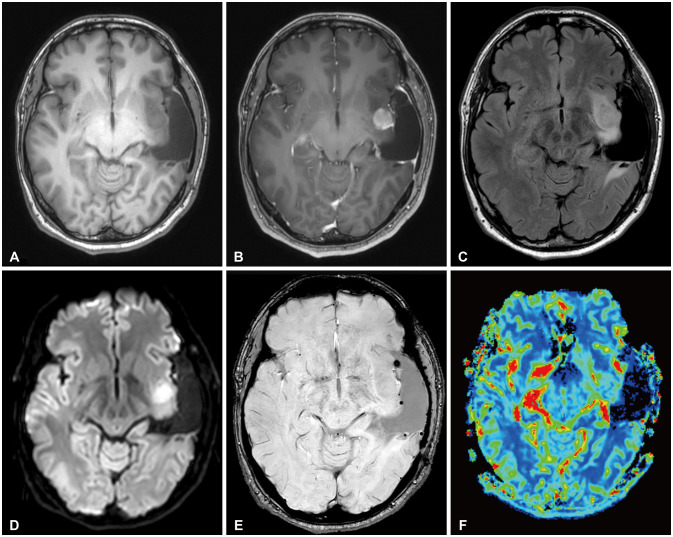

High-grade transformation of low-grade gliomas has long been a poor prognostic factor during therapy. In 2016, the World Health Organization (WHO) Classification of Tumors of the Central Nervous System (CNS) adopted isocitrate dehydrogenase (IDH) mutation status in the classification of diffuse astrocytomas. The 2021 classification denoted glioblastomas as IDH-wildtype and graded IDH-mutant astrocytomas as 2, 3, or 4. Gemistocytic morphology, a large proportion of residual tumor, the patient's age, and recurrence after radiotherapy were previously mentioned as risk factors for high-grade transformation of low-grade gliomas. We report a 34-year-old male patient initially diagnosed with IDH-mutant grade 2 astrocytoma according to the 2021 WHO classification of CNS tumors. As the first surgical resection achieved gross total resection on postoperative MRI, no adjuvant therapy was given and regular follow-up was planned. On 1-year follow-up MRI, two new enhancing nodular lesions appeared at the ipsilateral brain parenchyma abutting the surgical resection cavity. Salvage craniotomy achieved gross total resection, and the pathologic diagnosis was IDH-mutant WHO grade 4 astrocytoma. We describe this tumor in terms of the previous WHO classification to evaluate the risk of high-grade transformation and discuss possible risk factors leading to high-grade transformation of low-grade astrocytoma.